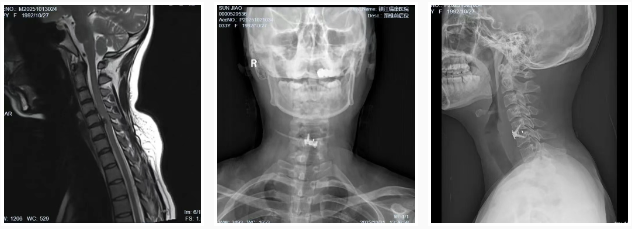

直到最近,情況急轉(zhuǎn)直下。她的左上肢開始出現(xiàn)持續(xù)性麻木,手指也變得不靈活,嚴重影響了工作和生活,甚至夜不能寐。門診收治入院后,經(jīng)過詳細檢查,診斷為“神經(jīng)根型頸椎病”,這意味著她的頸椎間盤已經(jīng)嚴重退化,壓迫到了神經(jīng)。如果不及時治療,可能會導(dǎo)致肢體癱瘓,后果不堪設(shè)想。孫女士最終接受了朱主任團隊為其定制的頸椎前路顯微鏡下椎間盤切除融合術(shù)(ACDF),手術(shù)很成功,術(shù)后她的麻木感和疼痛都得到了明顯的緩解 。

孫女士的案例并非個例。長期不正確的姿勢,如久坐、低頭,會導(dǎo)致頸椎間盤和韌帶承受巨大壓力,加速其退行性改變。我們發(fā)現(xiàn),許多青少年也因為姿勢不當,頸椎生理曲度變直,甚至出現(xiàn)反弓和后突的表現(xiàn),為日后埋下嚴重的健康隱患。這些早期退化的跡象,預(yù)示著頸椎病正在年輕化,不再是老年人的“專利”。